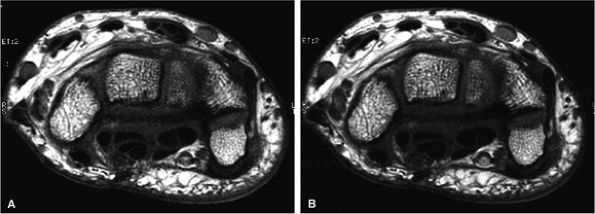

FIGURE 1.7 ● SENSE/ASSET acceleration × 2 with an eight-channel wrist array coil. Axial 2D fast spin-echo (TR 700, TE 16, ETL 2, slice thickness 2 mm, FOV 10 cm, 384 × 320 matrix, 15 slices). With ASSEST × 2 (A), scan time was 58 seconds. Without ASSET (B), scan time was 1 minute 54 seconds. The SNR reduction with ASSET is minimized due to the optimal coil g-factor.